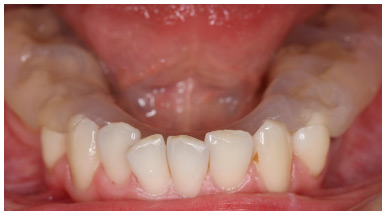

По результатам ТЭНС изготавливалась разобщающая зубные ряды каппа для постоянного использования, исключая время приема пищи и гигиенических мероприятий (Рис. 2,3).

Рис.2. Разобщающая каппа, вид с правой (а) и левой (б) сторон.

Рис. 3. Разобщающая каппа, приоткрытый рот.